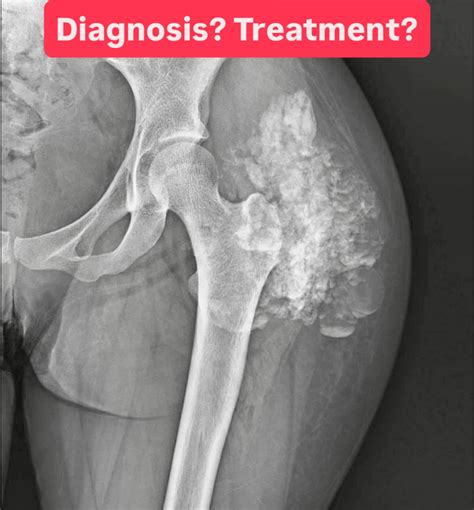

Osteoporosis Femur X Ray at Maddison Chidley blog